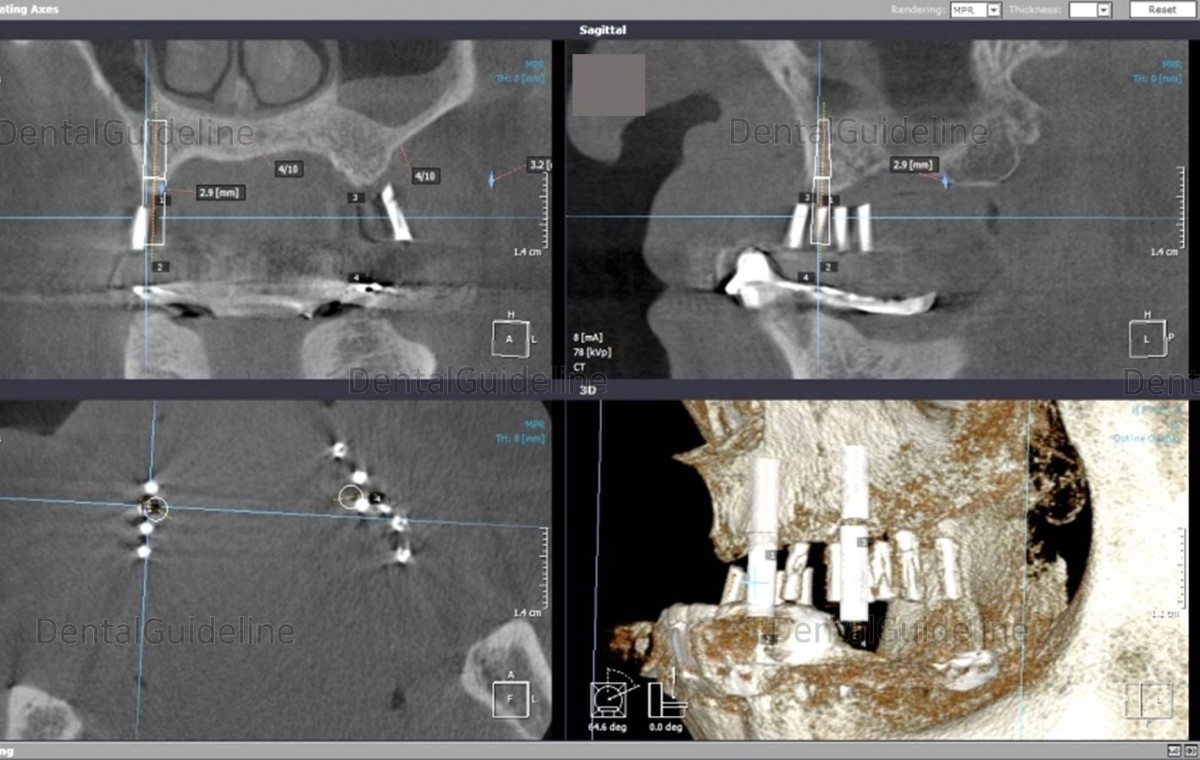

Check the angle between the two implants on the radiograph